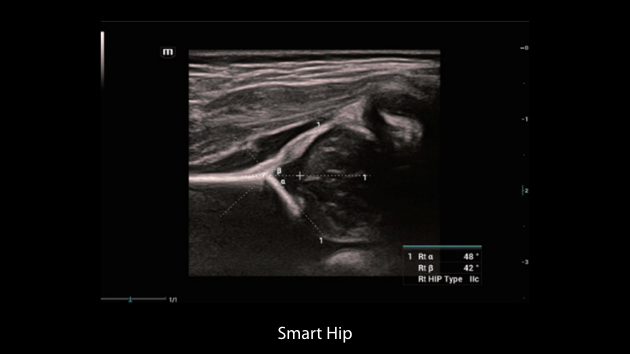

Gambar Klinis